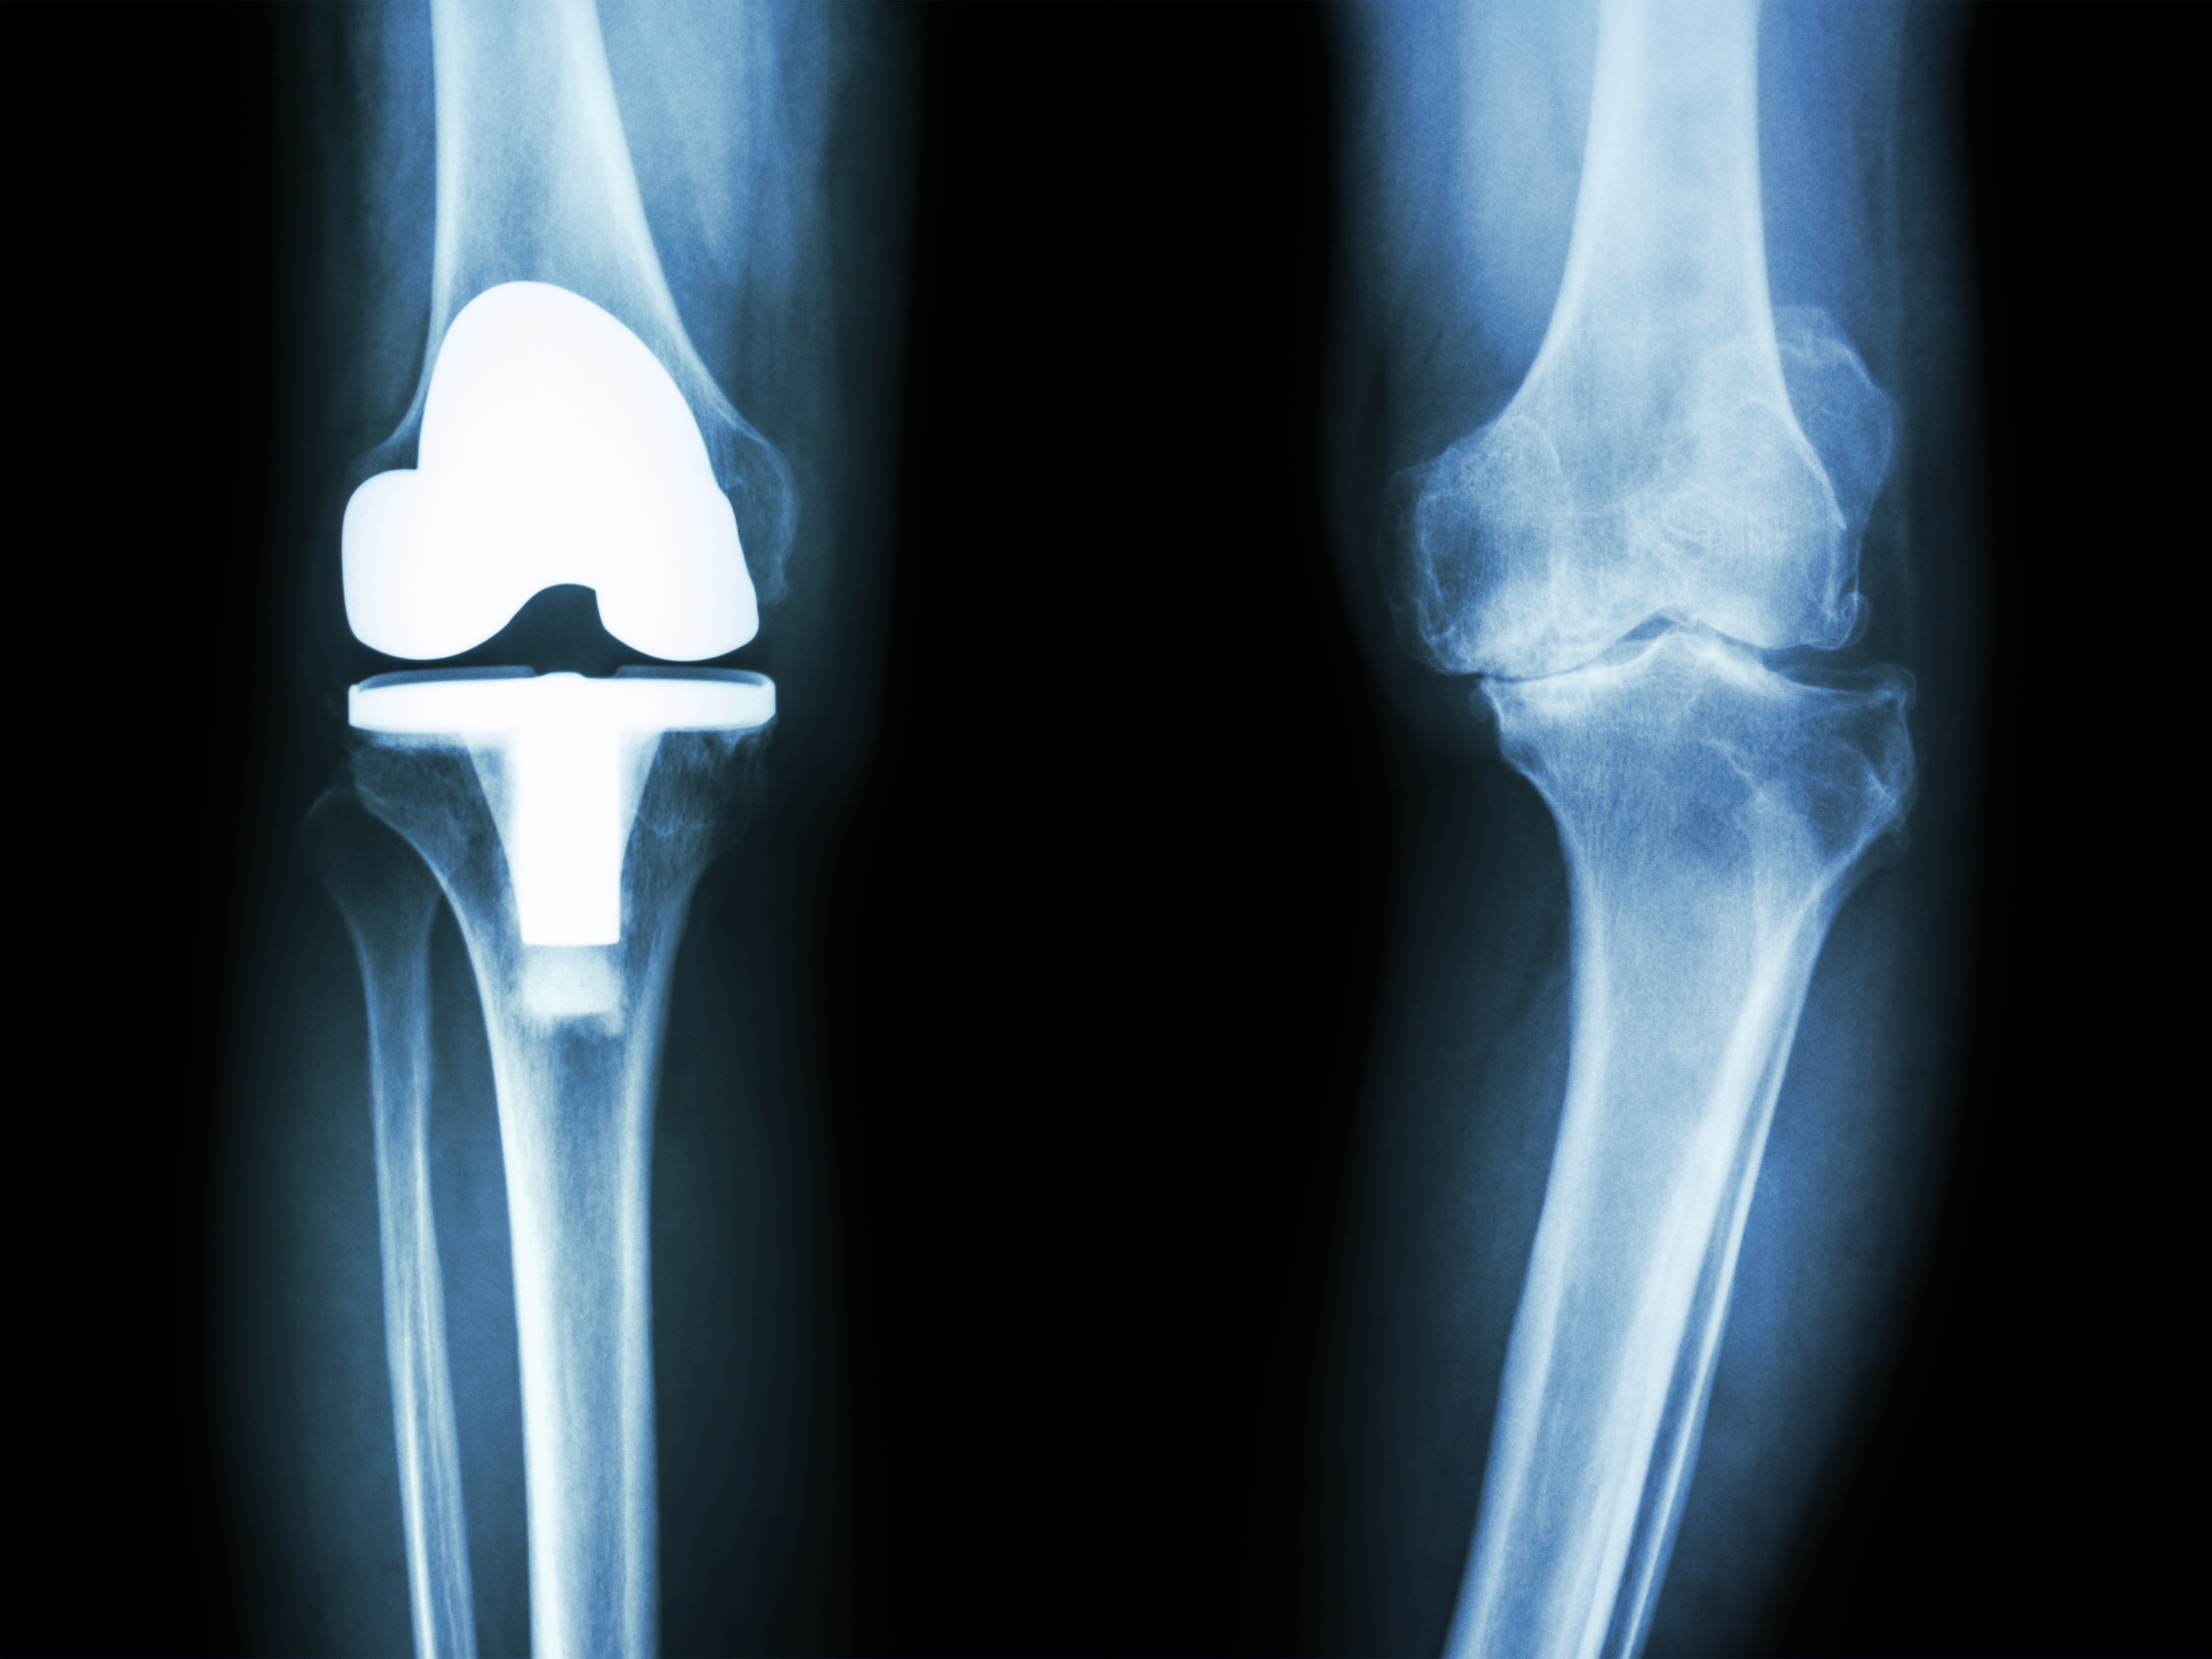

Knee replacement surgery, also known as knee arthroplasty, is a surgical procedure designed to alleviate chronic knee pain and improve joint function in individuals with severe knee damage. The surgery involves replacing the damaged or worn-out surfaces of the knee joint with artificial implants made of metal alloys, high-grade plastics, or polymers. These implants mimic the natural movement of the knee, providing stability and reducing pain.

The goal of knee replacement surgery is to restore mobility, relieve pain, and enhance the overall quality of life for individuals suffering from knee conditions that have not responded well to non-surgical treatments.

Total Knee Replacement (TKR) is a highly effective procedure that can significantly improve the quality of life for patients suffering from chronic knee pain. Proper post-operative care, including medication adherence, physiotherapy, and lifestyle modifications, plays a crucial role in ensuring a successful recovery. If you or a loved one are considering knee replacement surgery, consult an orthopedic specialist to explore the best treatment options.